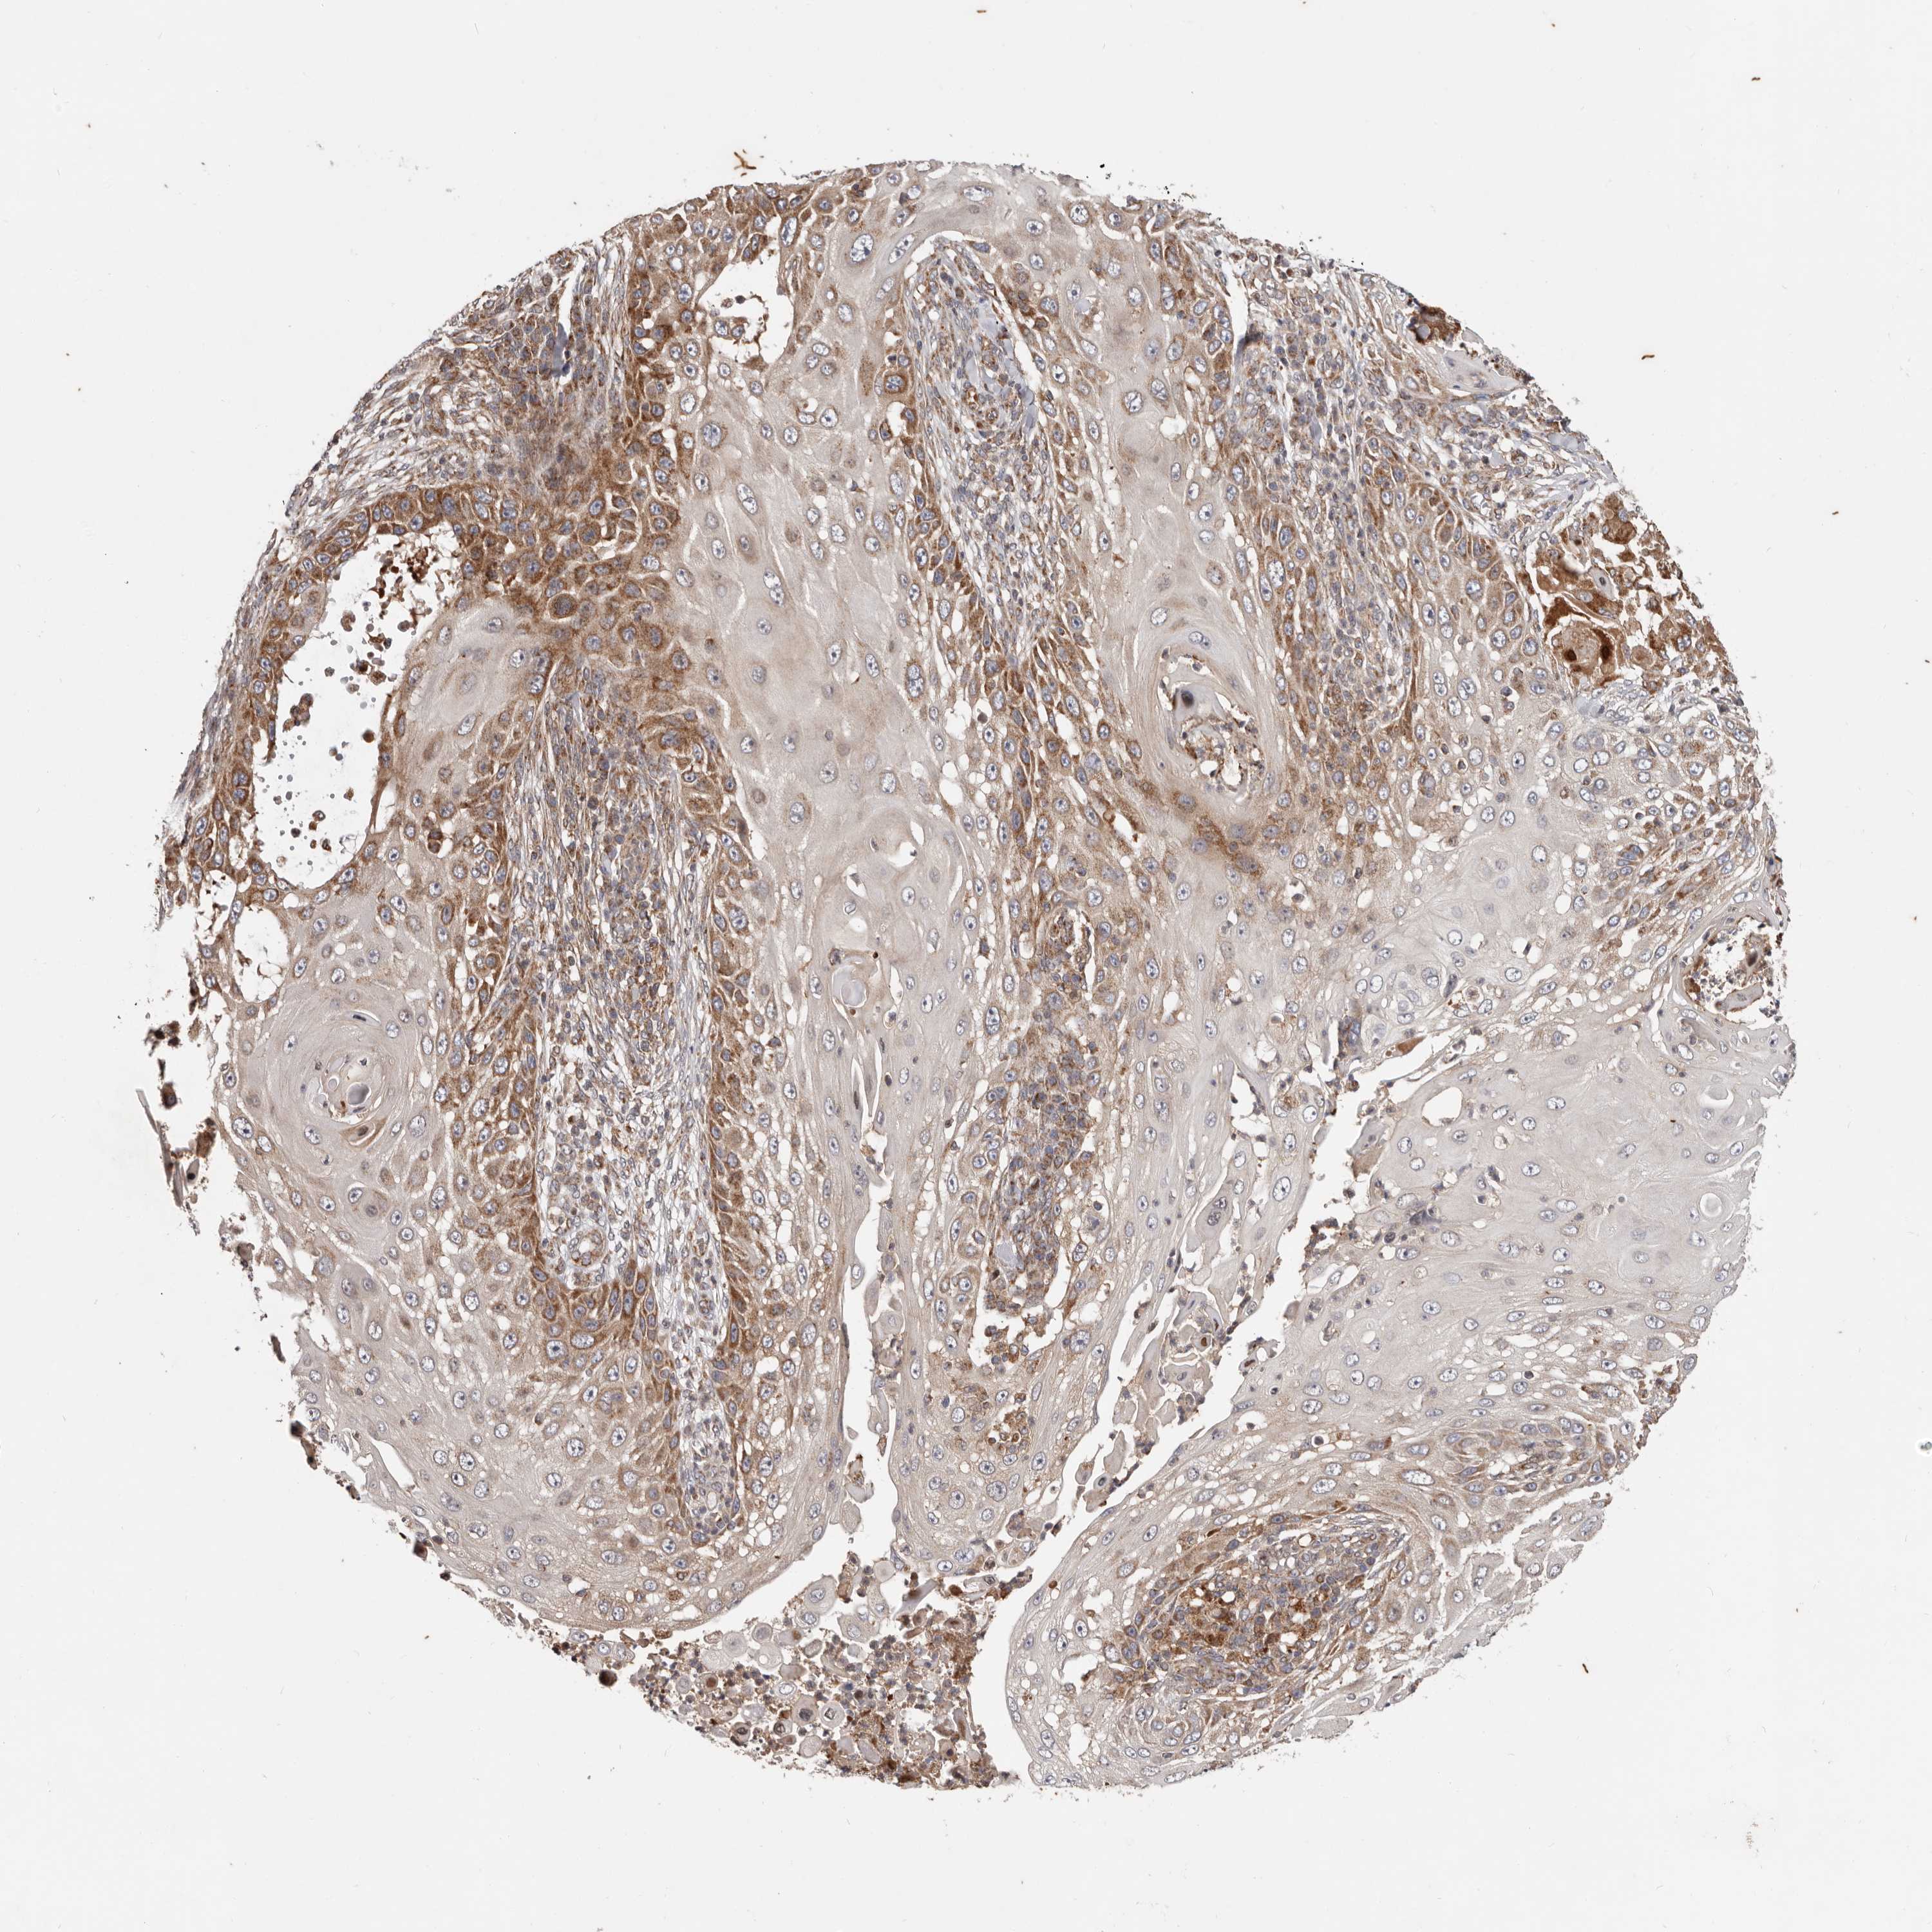

SKIN CANCER - Protein expressioni

A mouse-over function shows sample information and annotation data. Click on an image to view it in a full screen mode. Samples can be filtered based on level of antibody staining by selecting one or several of the following categories: high, medium, low and not detected. The assay and annotation is described here.

Each image is clickable and will lead to virtual microscopy that enables deeper exploration of all samples and also displays staining intensity scores, fraction scores and subcellular localization as well as patient and tissue information for each sample.

Antibody HPA029133

Squamous cell carcinoma, NOS